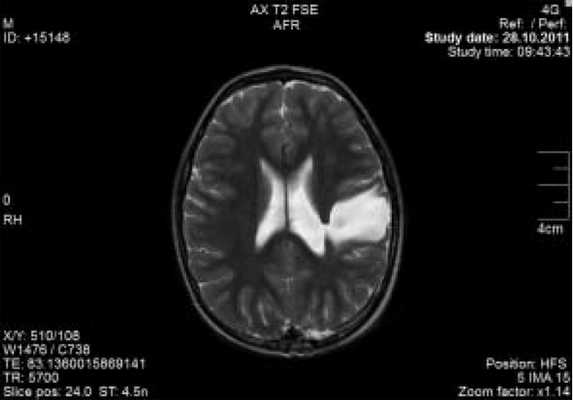

Примеры сочетания ДЦП, фокальной эпилепсии и наличия эпилептиформных разрядов типа ДЭРД нередки в клинической практике. В качестве примера приводим данные магнитно-резонансной томографии (МРТ) и ЭЭГ пациента Ш.И. (рис. 3, 4).

Рис. 3. Магнитно-резонансная томограмма больного Ш.И., 7 лет.

Диагноз: «Детский церебральный паралич, гемипаретическая форма (правосторонний гемипарез). Симптоматическая фокальная эпилепсия с правосторонними гемиконвульсивными, адверсивными, диалептическими и миоклонически-астатическими приступами. Порэнцефалическая киста теменно-височной области слева».